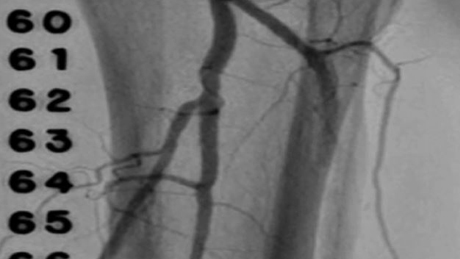

Peripheral Rotablator™

Rotational Atherectomy System

Case Studies